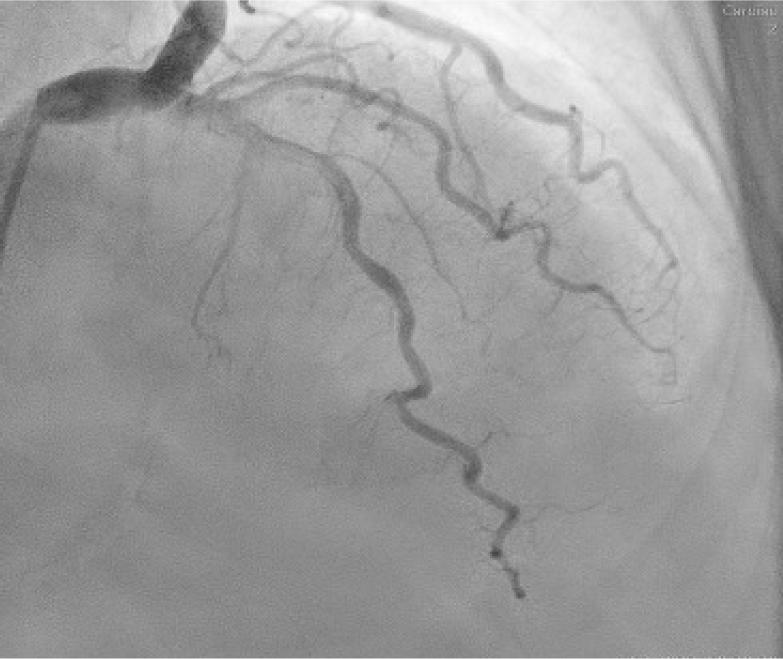

A follow-up coronary angiogram demonstrated complete dissolution of RCA thrombus, a moderate atherosclerotic stenosis (50%–60%) (Fig. 5) in the distal segment, right before crux-cordis and the persistence of the slow flow phenomenon in the coronary artery tree because of diffuse ectasia (Figs. 6, 7).

Postero-anterior caudal projection of the left coronary artery—1 month later. This view optimally projects the left main coronary artery (mid-distal segment) and the left circumflex, in which no significant atherosclerotic lesions are seen. Note also the diffuse ectasia present in both arteries.